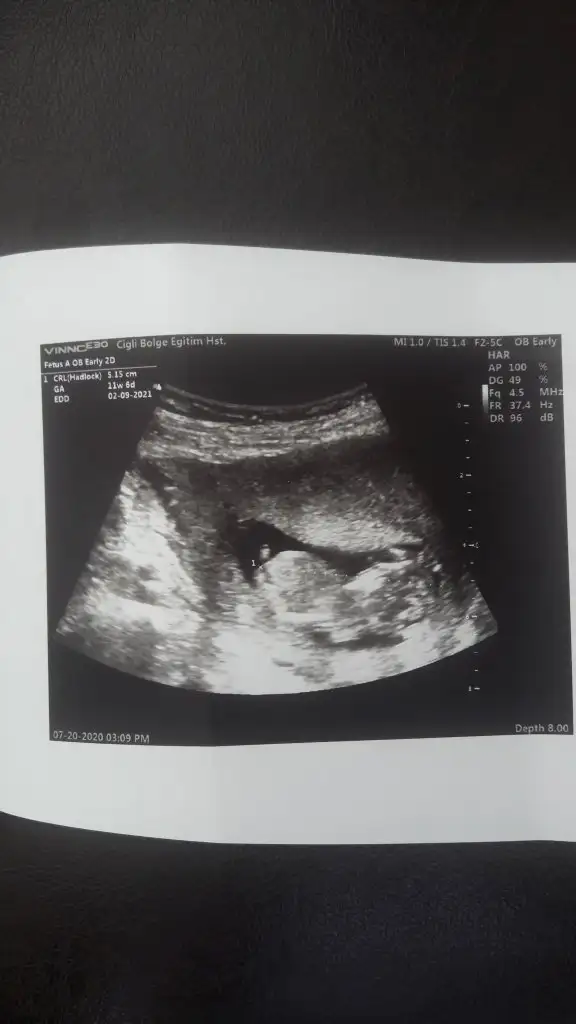

Kizz11 hafta 1 ama dr 12 hafta 1 gozukmekte dedi tahminde bulunurmusunuz

Kizz :)Bir başka ultrason istemiştiniz bunlar var elimde bacaklarini bağlamışti öylece duruyorduheyecanla yorumunuzu bekliyorumm Ikra meyra

Benimki 12+2 atsam bakarmısınız acabaCanım çok net değil emin olamadım sanki sanki erkek olursa 13 hafta paylaş cnm